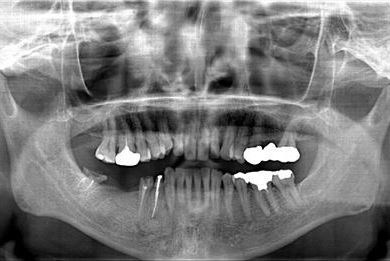

| 性別/年齢 | 男性 / 57歳 | ||||||||||||||||||||||||||||||||

| 主訴 | 右奥歯のブリッジが取れ、支柱の2本の歯が痛むため、インプラント治療を希望。 | ||||||||||||||||||||||||||||||||

| 治療内容 | インプラント2本、ハイブリッドセラミック2本 | ||||||||||||||||||||||||||||||||

| 総治療費 | 533,610円 | ||||||||||||||||||||||||||||||||

| 治療期間 | 1年0ヶ月 |